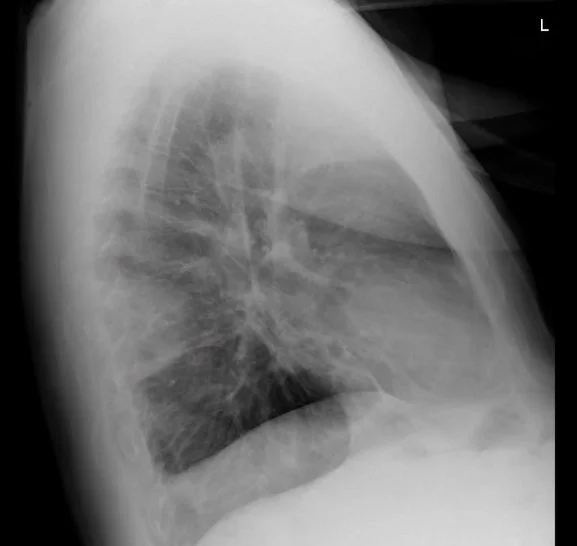

Below are her CXR and a photo of the oropharynx. Hint: the lateral xray holds the key.

do you notice a peripheral wedge shaped opacity?

Our patient had a wedge-shaped defect seen best on the lateral CXR.  This “ Hampton’s hump”  is suggestive of a pulmonary embolus since it  touches  the pleura.  If this is combined with the image of oral ulcers, it suggests a more systemic disease.  Our patient had lupus with a circulating lupus anticoagulant causing the pulmonary embolus.